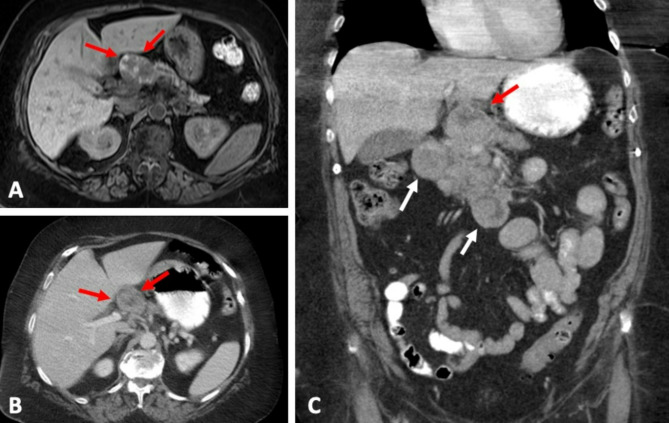

Results: pACC tended to present as a solid (31/49, 63.3%) pancreatic head mass (26/49, 53.1%) with ill-defined margins (32/49, 65.3%) and median maximal diameter of 4.1 cm (IQR, 2.9-6.2). Majority of lesions were hypo- or isodense (38/49, 77.6%) compared to normal pancreatic parenchyma, with heterogenous (39/49, 79.6%) enhancement pattern. Biliary ductal dilatation was uncommon, with pancreatic ductal dilatation in 22.4% (11/49) and common bile duct dilatation in 14.3% (7/49). Intralesional calcifications were seen in 6.1% (3/49). Metastasis was present in 71.4% (35/49) of patients at the time of diagnosis. On MRI, 88.9% (16/18) demonstrated diffusion restriction and 59.1% (13/22) with heterogenous enhancement. On multivariate analysis, the imaging presence of T1 hyperintensity (p = 0.02), hypoattenuating necrotic components (p = 0.02), and splenic vein invasion (p = 0.04) were associated with worse survival.

Conclusion: Pancreatic acinar cell carcinoma is a rare pancreatic neoplasm that often presents as a large ill-defined heterogeneously enhancing mass without biliary ductal dilation. T1 hyperintensity, presence of hypoattenuating necrotic components, and splenic vein invasion were independent predictors of survival.